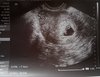

fajnie już coś wiesz , wszystko dobrzeJestem po wizycie moja gin wyliczyła termin na 6 styczeń za dwa tygodnie kolejna wizyta i będzie książeczka. Listę badań do zrobienia. Zamiast zwykłego kwasu foliowego zaleciła pregna start z witaminami i kwasem foliowy.. Serduszko już biło.. Od czerwca idę na l4 względu na fizyczną pracę jak i uplaly brak umnie klimy nawed 20 c to masakra jest

Cześć fasolkoJestem po wizycie moja gin wyliczyła termin na 6 styczeń za dwa tygodnie kolejna wizyta i będzie książeczka. Listę badań do zrobienia. Zamiast zwykłego kwasu foliowego zaleciła pregna start z witaminami i kwasem foliowy.. Serduszko już biło.. Od czerwca idę na l4 względu na fizyczną pracę jak i uplaly brak umnie klimy nawed 20 c to masakra jest